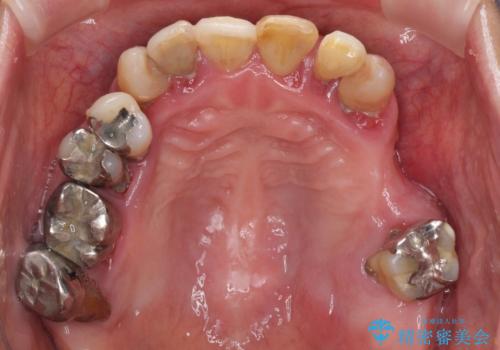

- 歯周病を放置したことで奥歯が抜け、前歯も痛くなってきたとのことで来院された患者様です。

奥歯はほとんどを抜歯しなければならない状態であり、抜歯をせずに済む歯も歯周外科処置や矯正治療を行う必要がある状態でした。

歯を抜かないといけない部分はインプラントとオールセラミッククラウンにより咬合を回復させ、歯周外科処置を行う歯については、同じくオールセラミッククラウンにて補綴治療を行うこととしました。